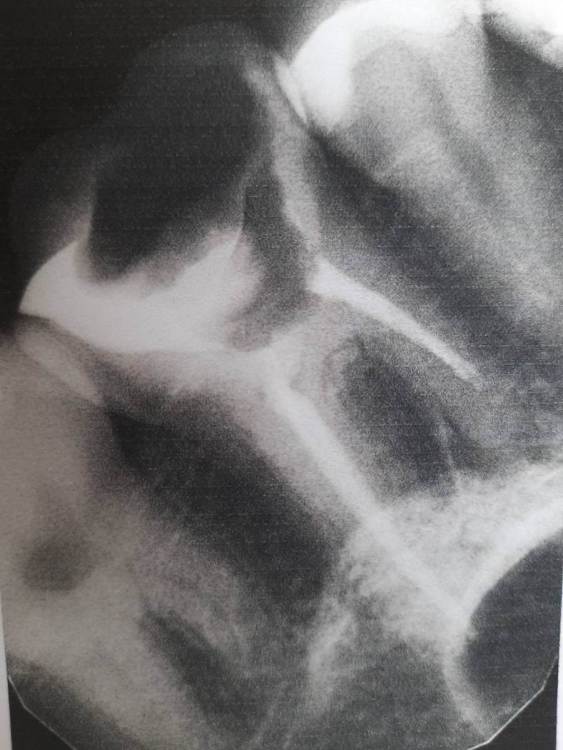

Добрый день! На верхушке корня 26 зуба была обнаружена гранулема.  Проведена ревизия каналов, временное пломбирование пастой каласепт, через две недели постоянное гуттаперчевыми штифтами. Постпломбировочные боли вторую неделю довольно сильные. Есть ли шанс спасти зуб?

Снимок после лечения только такой

изображение_viber_2021-04-27_09-45-56.jpg